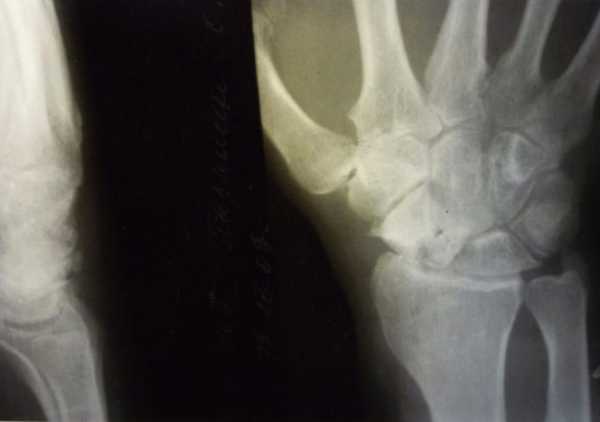

Перелом запястья

При падении человек выставляет руку вперед, чтобы защититься от удара о землю. Это приводит к переломам, которыми страдают люди с активным образом жизни. К ним относятся спортсмены, кроссмены, мотоциклисты. Нередко причиной падения являются погодные условия – гололед, снег, дождь. Пострадавший испытывает острую боль, появляется отечность, краснота. Требуется срочное обращение в больницу, так как самолечение приведет к обездвиженности сустава и инвалидности.

Переломы кисти встречаются часто: в непогоду процент травм возрастает. Связано это с недостаточной прочностью костей, большими нагрузками на них. Резкий удар заставляет человека непроизвольно притормозить ладонью, что приводит к перелому со смещением. В верхней части ладонной поверхности образуется припухлость. Если удар пришелся на тыльную сторону, то диагностируют повреждение лучевой кости. В обоих случаях наступает опасность болевого шока, поэтому человека немедленно госпитализируют.

Симптомы, диагностика, лечение

Первый симптом перелома – это острая боль. Мягкие ткани начинают отекать, притронуться к месту повреждения становится болезненно, появляются гематомы. Пошевелить пальцами трудно из-за болезненных ощущений. Появляется выпуклость в районе лучезапястного сустава, попытка сделать движение кистью сопровождается характерным хрустом, кость на запястье выпирает. Оказание первой помощи подразумевает фиксацию поврежденной конечности, наложение холодного компресса к месту травмы.

Для диагностики перелома доктор ощупывает участок травмы, проводится рентген. В тяжелых случаях при раздроблении костей делается МРТ-диагностика. После выявления наличия осложнений, определения поломанной кости, определяется программа лечения.

Первым образом проводится операция по извлечению частей косточек. По возможности хирург проводит ювелирную работу по сбору остатков сустава для полноценной жизни больного. В более легких случаях оперативное вмешательство не требуется, и накладывается гипсовая повязка до полного сращивания костей. В период лечения требуется полная неподвижность конечности.